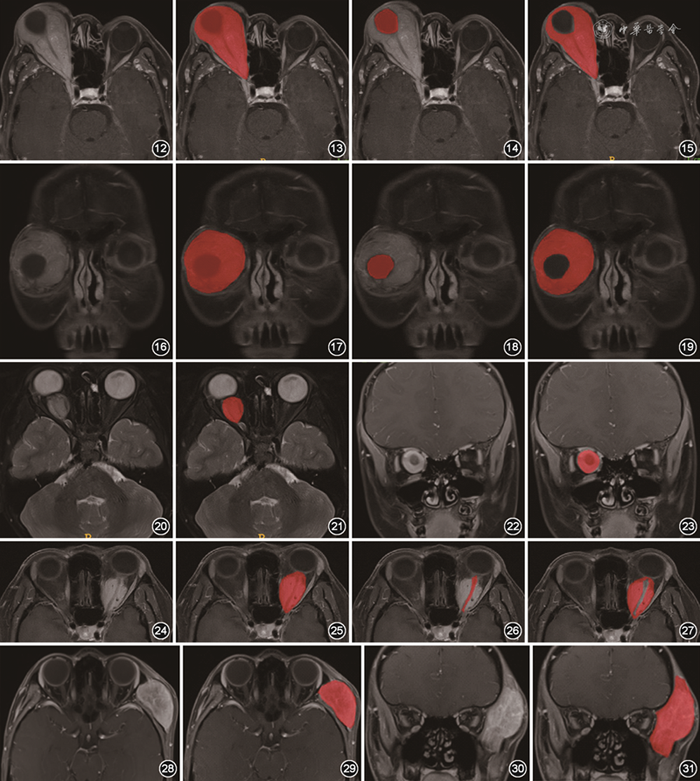

(3)包绕眼球的肿块。当肿块包绕眼球不超过1/2眼周时,采用直接勾画的方式完成标注;当肿块生长超过1/2眼周时,勾画时要特别注意“首尾重叠”,避免遗漏病变;当肿块完全包绕眼球时,结合横断面T2WI及增强T1WI图像进行标注,首先标注肿块整体和眼球,然后单独标注眼球,前者减去后者即为肿块,勾画示意图见图12~19。

图12~19 眼眶肿块完全包绕眼球的勾画示意图。病理证实为淋巴瘤,肿块完全包绕眼球。首先标注肿块整体和眼球(图12,13),再单独标注眼球(图14),两者减影后获得标注肿块的图像(图15)。图16~19为相应冠状面图像